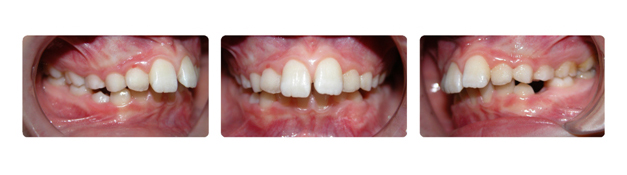

| فک بالا جلوتراز فک پایین و روی دندانهای فک پایین قرار گرفته است وچون از سن رشد نگذشته در ابتدا با پلاک متحرک درمان شروع میشود . |

![]() |

| در حین استفاده از پلاکهای متعدد متحرک درمان ارتدونسی ثابت نیز آغاز میشود: |